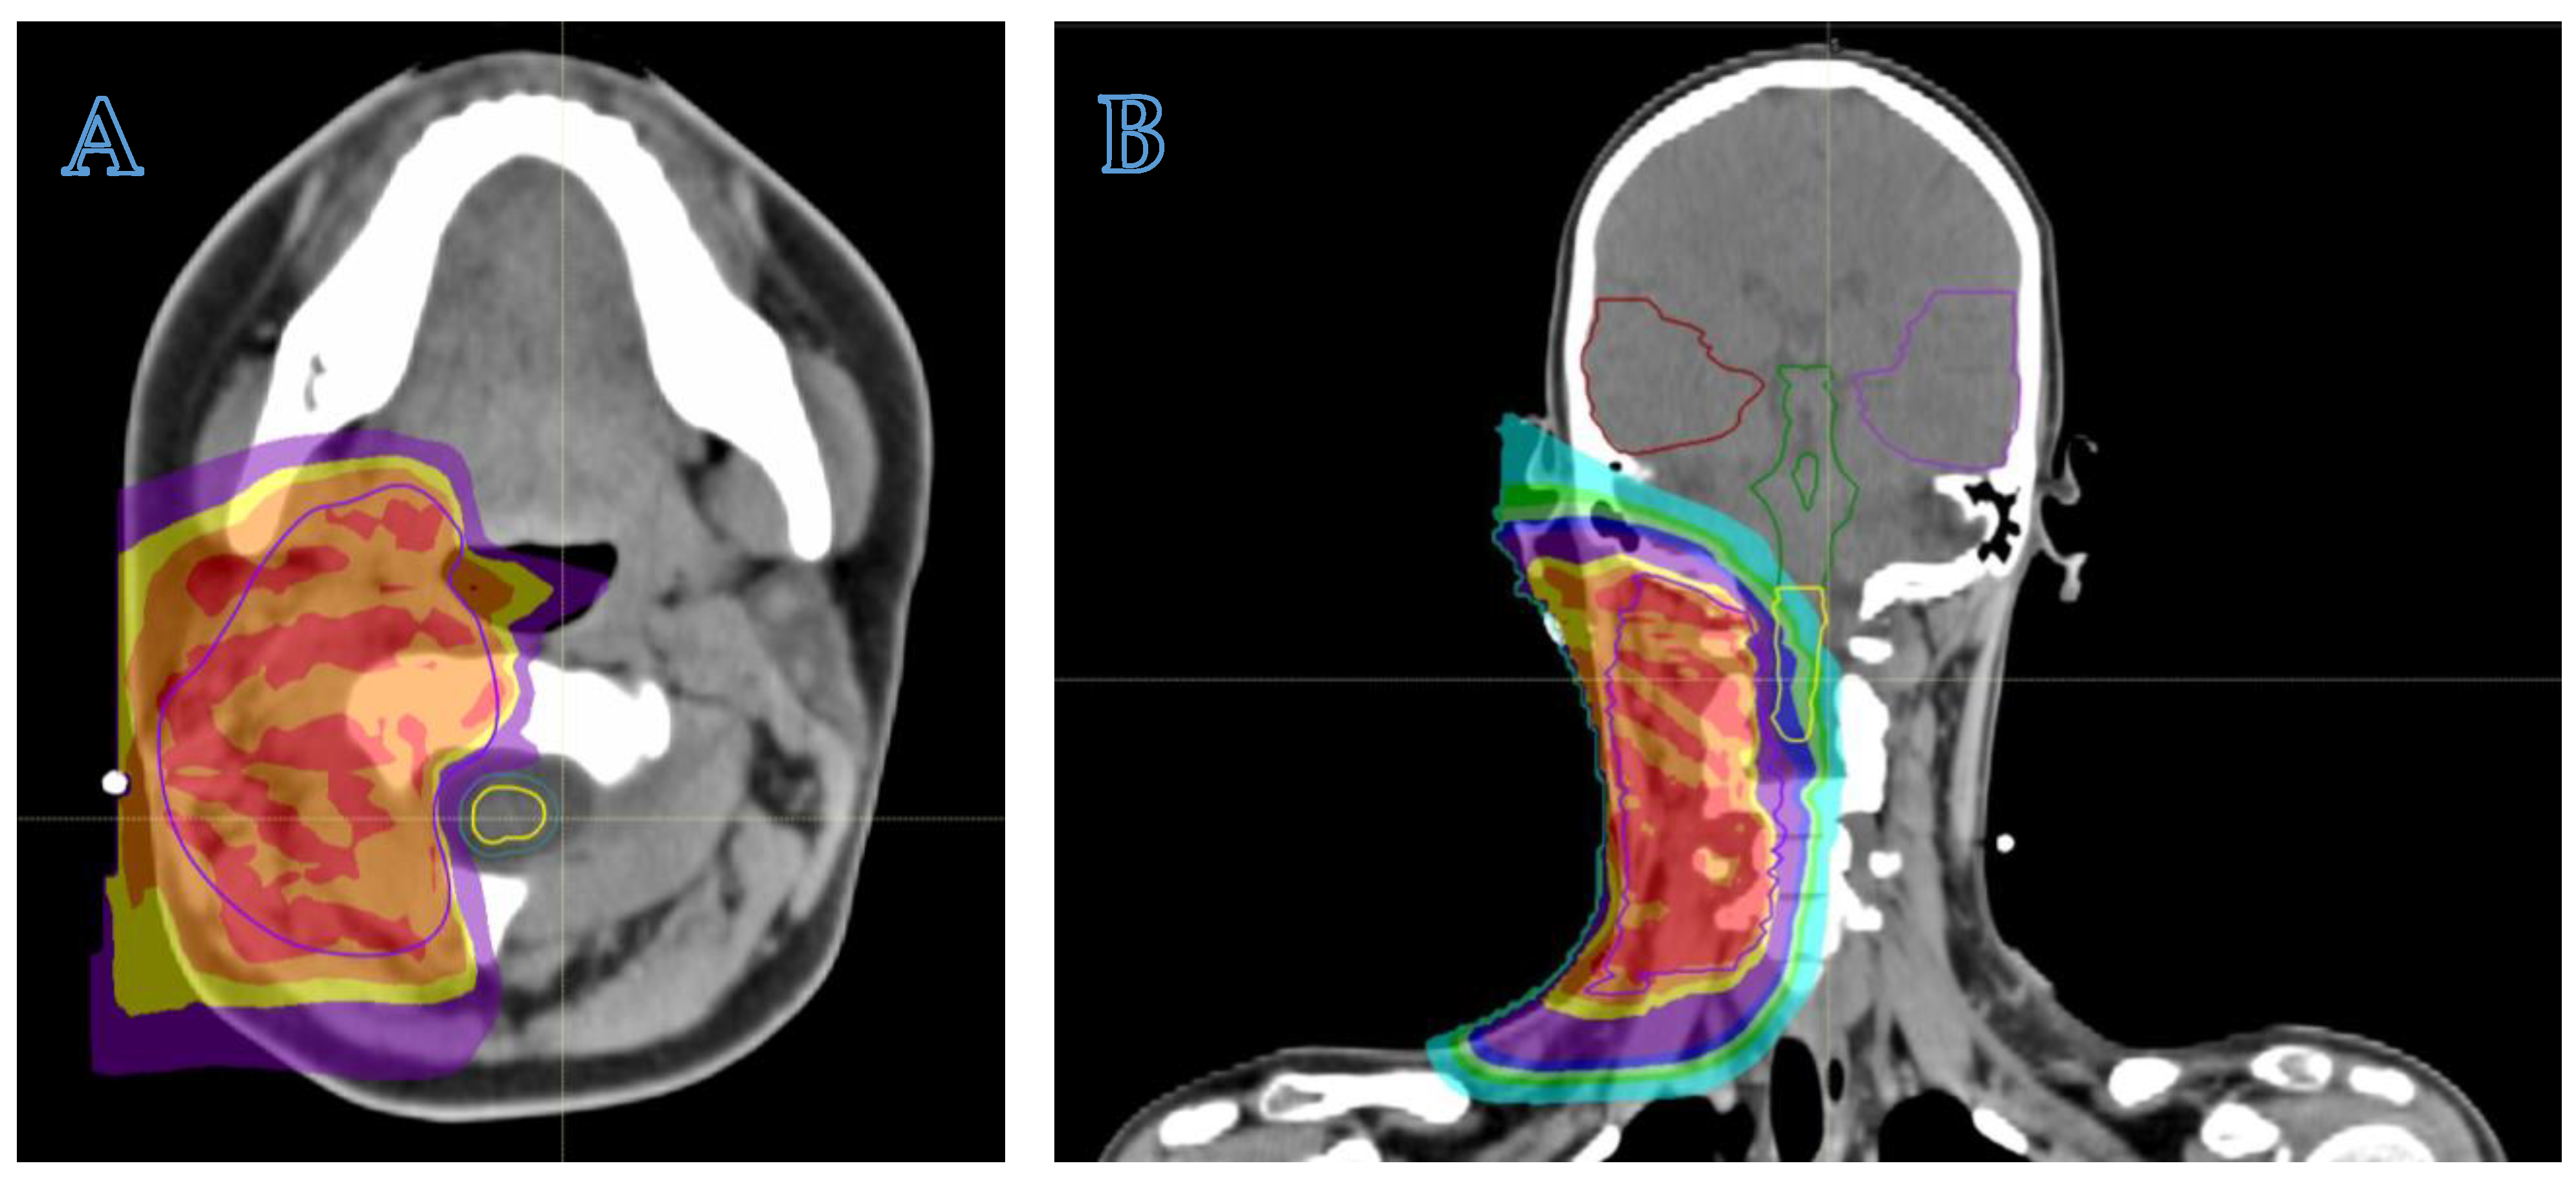

Figure 2.

The axial (A) and coronal (B) views of a proton beam plan, utilizing a pencil scanning proton beam therapy (PBS-PBT) technique, illustrate the treatment of a 13-year-old girl with epithelioid sarcoma. The images demonstrate that the clinical target volume (CTV) is adequately covered by the high doses of radiotherapy (isodoses of 100%, 98% and 95% of the prescribed dose, respectively, indicated in red, orange and yellow). Meanwhile, the low doses of radiotherapy (isodoses of 60%, 50% and 25% in light green, green and blue, respectively) spare the organs at risk located in the supra- and subtentorial regions and the contralateral laterocervical region.

- The anatomical site and the subsequent fragility of the surrounding organs at risk to potential radiation damage is a critical matter. The head–neck, craniofacial, intra-abdominal, pelvic, and paravertebral regions may be considered elective sites, where PBT can minimize radiation exposure to nearby organs (Figure 2). In addition to minimizing the risk of late sequelae, the reduced irradiation of surrounding tissues (mucosae, for example) may also reduce acute toxicity and thus improve compliance with intensive multimodal treatment including concomitant chemotherapy. While PBT may be less indicated for extremity tumors, exceptions should be made for young patients due to the potential for preserving growth plate cartilage and the lymphatic and vascular–nerve pathways present in the limbs.

- The physical properties of protons allow for a significant escalation in dose, potentially up to approximately 60 Gy Relative Biological Effectiveness (RBE), in the treatment of radioresistant histotypes, such as Malignant Peripheral Nerve Sheath Tumors (MPNSTs) (see Figure 3).